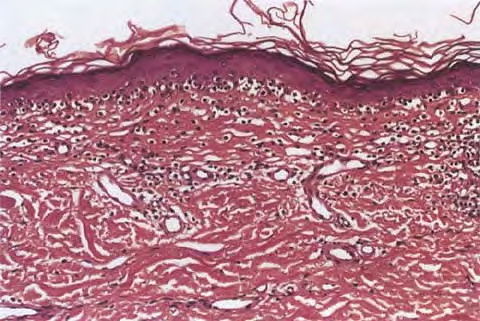

Mycosis Fongoïde =التفطر الكمئي